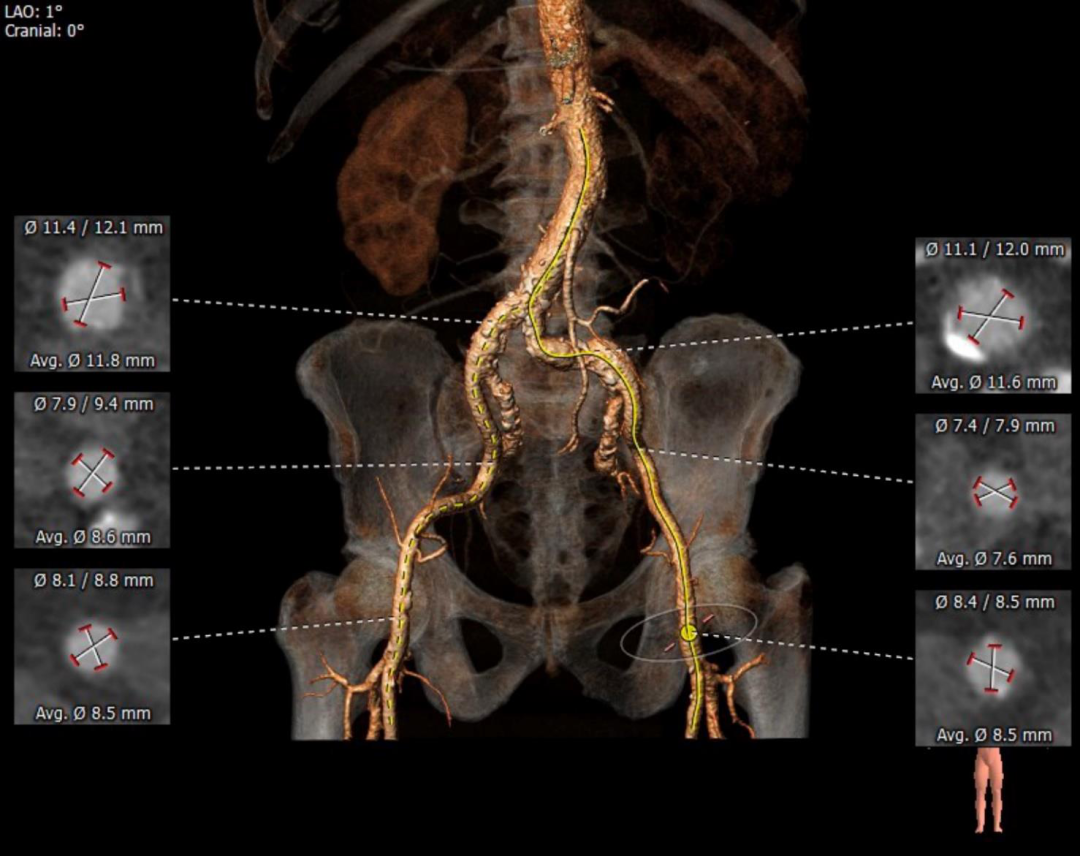

左右冠开口高度可,右冠多发钙化。

瓦氏窦内径可、窦管交界内径可。升主内径可,主动脉瓣环与水平面夹角可,主动脉弓角度与宽度可。

③血管入路方面,双侧股髂总直径可,左髂总位置形态扭曲并伴有瘤样扩张。